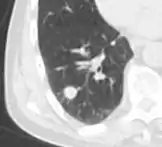

A "notch sign".[9]

A triangular perifissural node can be diagnosed as a benign lymph node.[9]